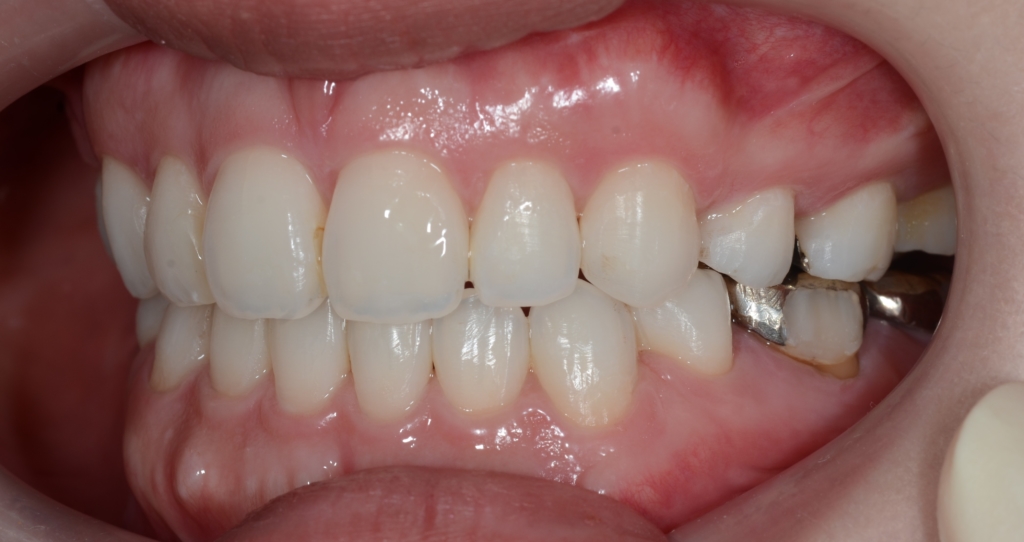

【After】

矯正後の状態をレントゲン写真で確認すると、

横顔や口元は患者さんの希望通りにスッキリして、満足してもらえました。

術前も口元にEラインを引くことが出来ました(レントゲン参照)が、お顔全体のバランスという意味で、同じEラインであっても術前と術後ではスッキリ感が異なります。

最後に、矯正治療前後のと「口元の写真」「レントゲン写真」「歯並び」の比較をお見せしましょう。

口元が飛び出た感じも無くなりました

お口を閉じた時のオトガイ部のシワも、治療後は無くなりました